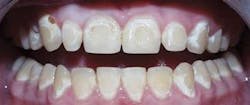

A new system for defining caries, beginning with subclinical decay to pulpal decay, has been developed by Pitts7 (Figure 1). He has defined caries with four major classifications:

1 Subclinical decay

2 Visible and invisible enamel decay

3 Visible and invisible dentin decay

4 Pulpal decay

These four stages have implications for today’s treatments.8 Figure 1 is an adaptation of the above reference, and Figure 2 shows how each of these four stages fits into a system of assessment and treatment. Each stage corresponds to either a medical treatment model, a surgical intervention model, or a combination. Medical management predominates for subclinical and enamel decay, while surgical intervention predominates for dentin decay and pulpal decay.